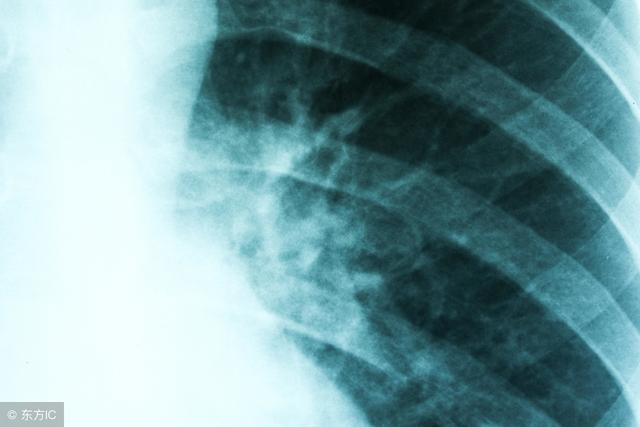

接下来我们来了解一下,鉴别支气管扩张的方法,因为支气管扩张会有很多的症状,所以要想辨别清楚,也是比较困难的,今天我们就来了解一下,如果是慢性支气管炎的话,大部分会出现在中年以上的患者,冬春季节会出现咳嗽,咳痰,还会伴有喘息,多为白色粘液痰,而且发生感染的时候会有浓痰。那么除了这之外,肺结核就会表现出低热,盗汗,全身无力,消瘦等症状,所以每一种症状的不同或是疾病的不同,表现方法又会有所不同,治疗起来也就会不同。